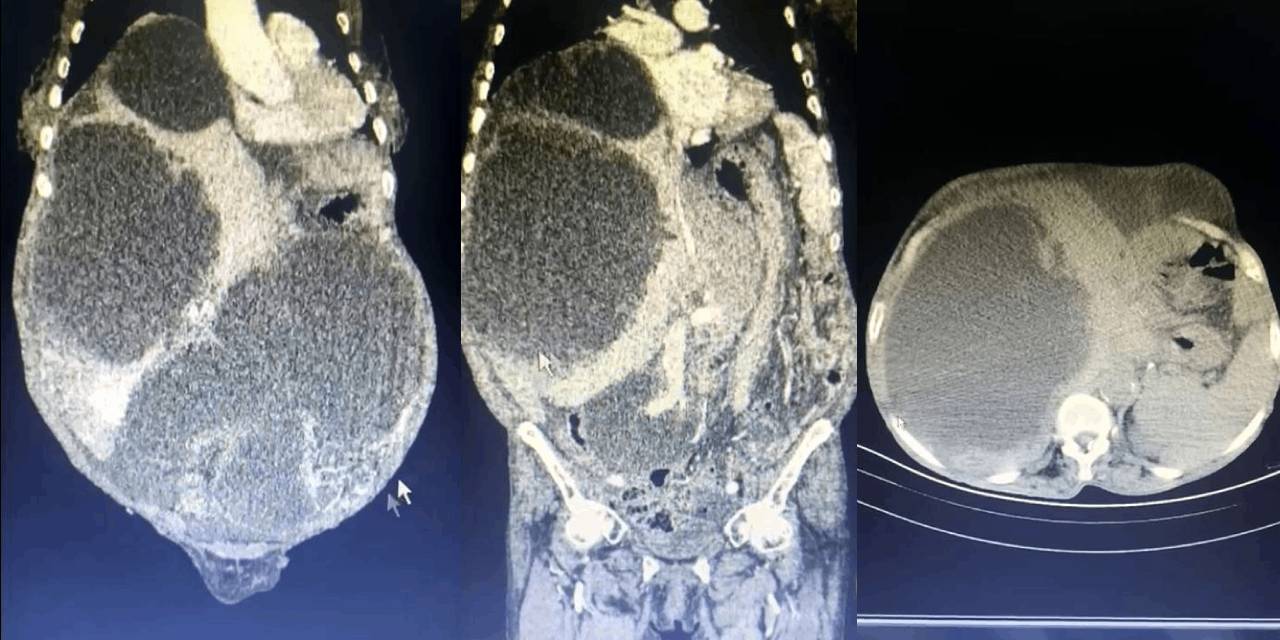

Tüm karnı kist kapladı! Doktorlar bile böyle bir şey görmedi